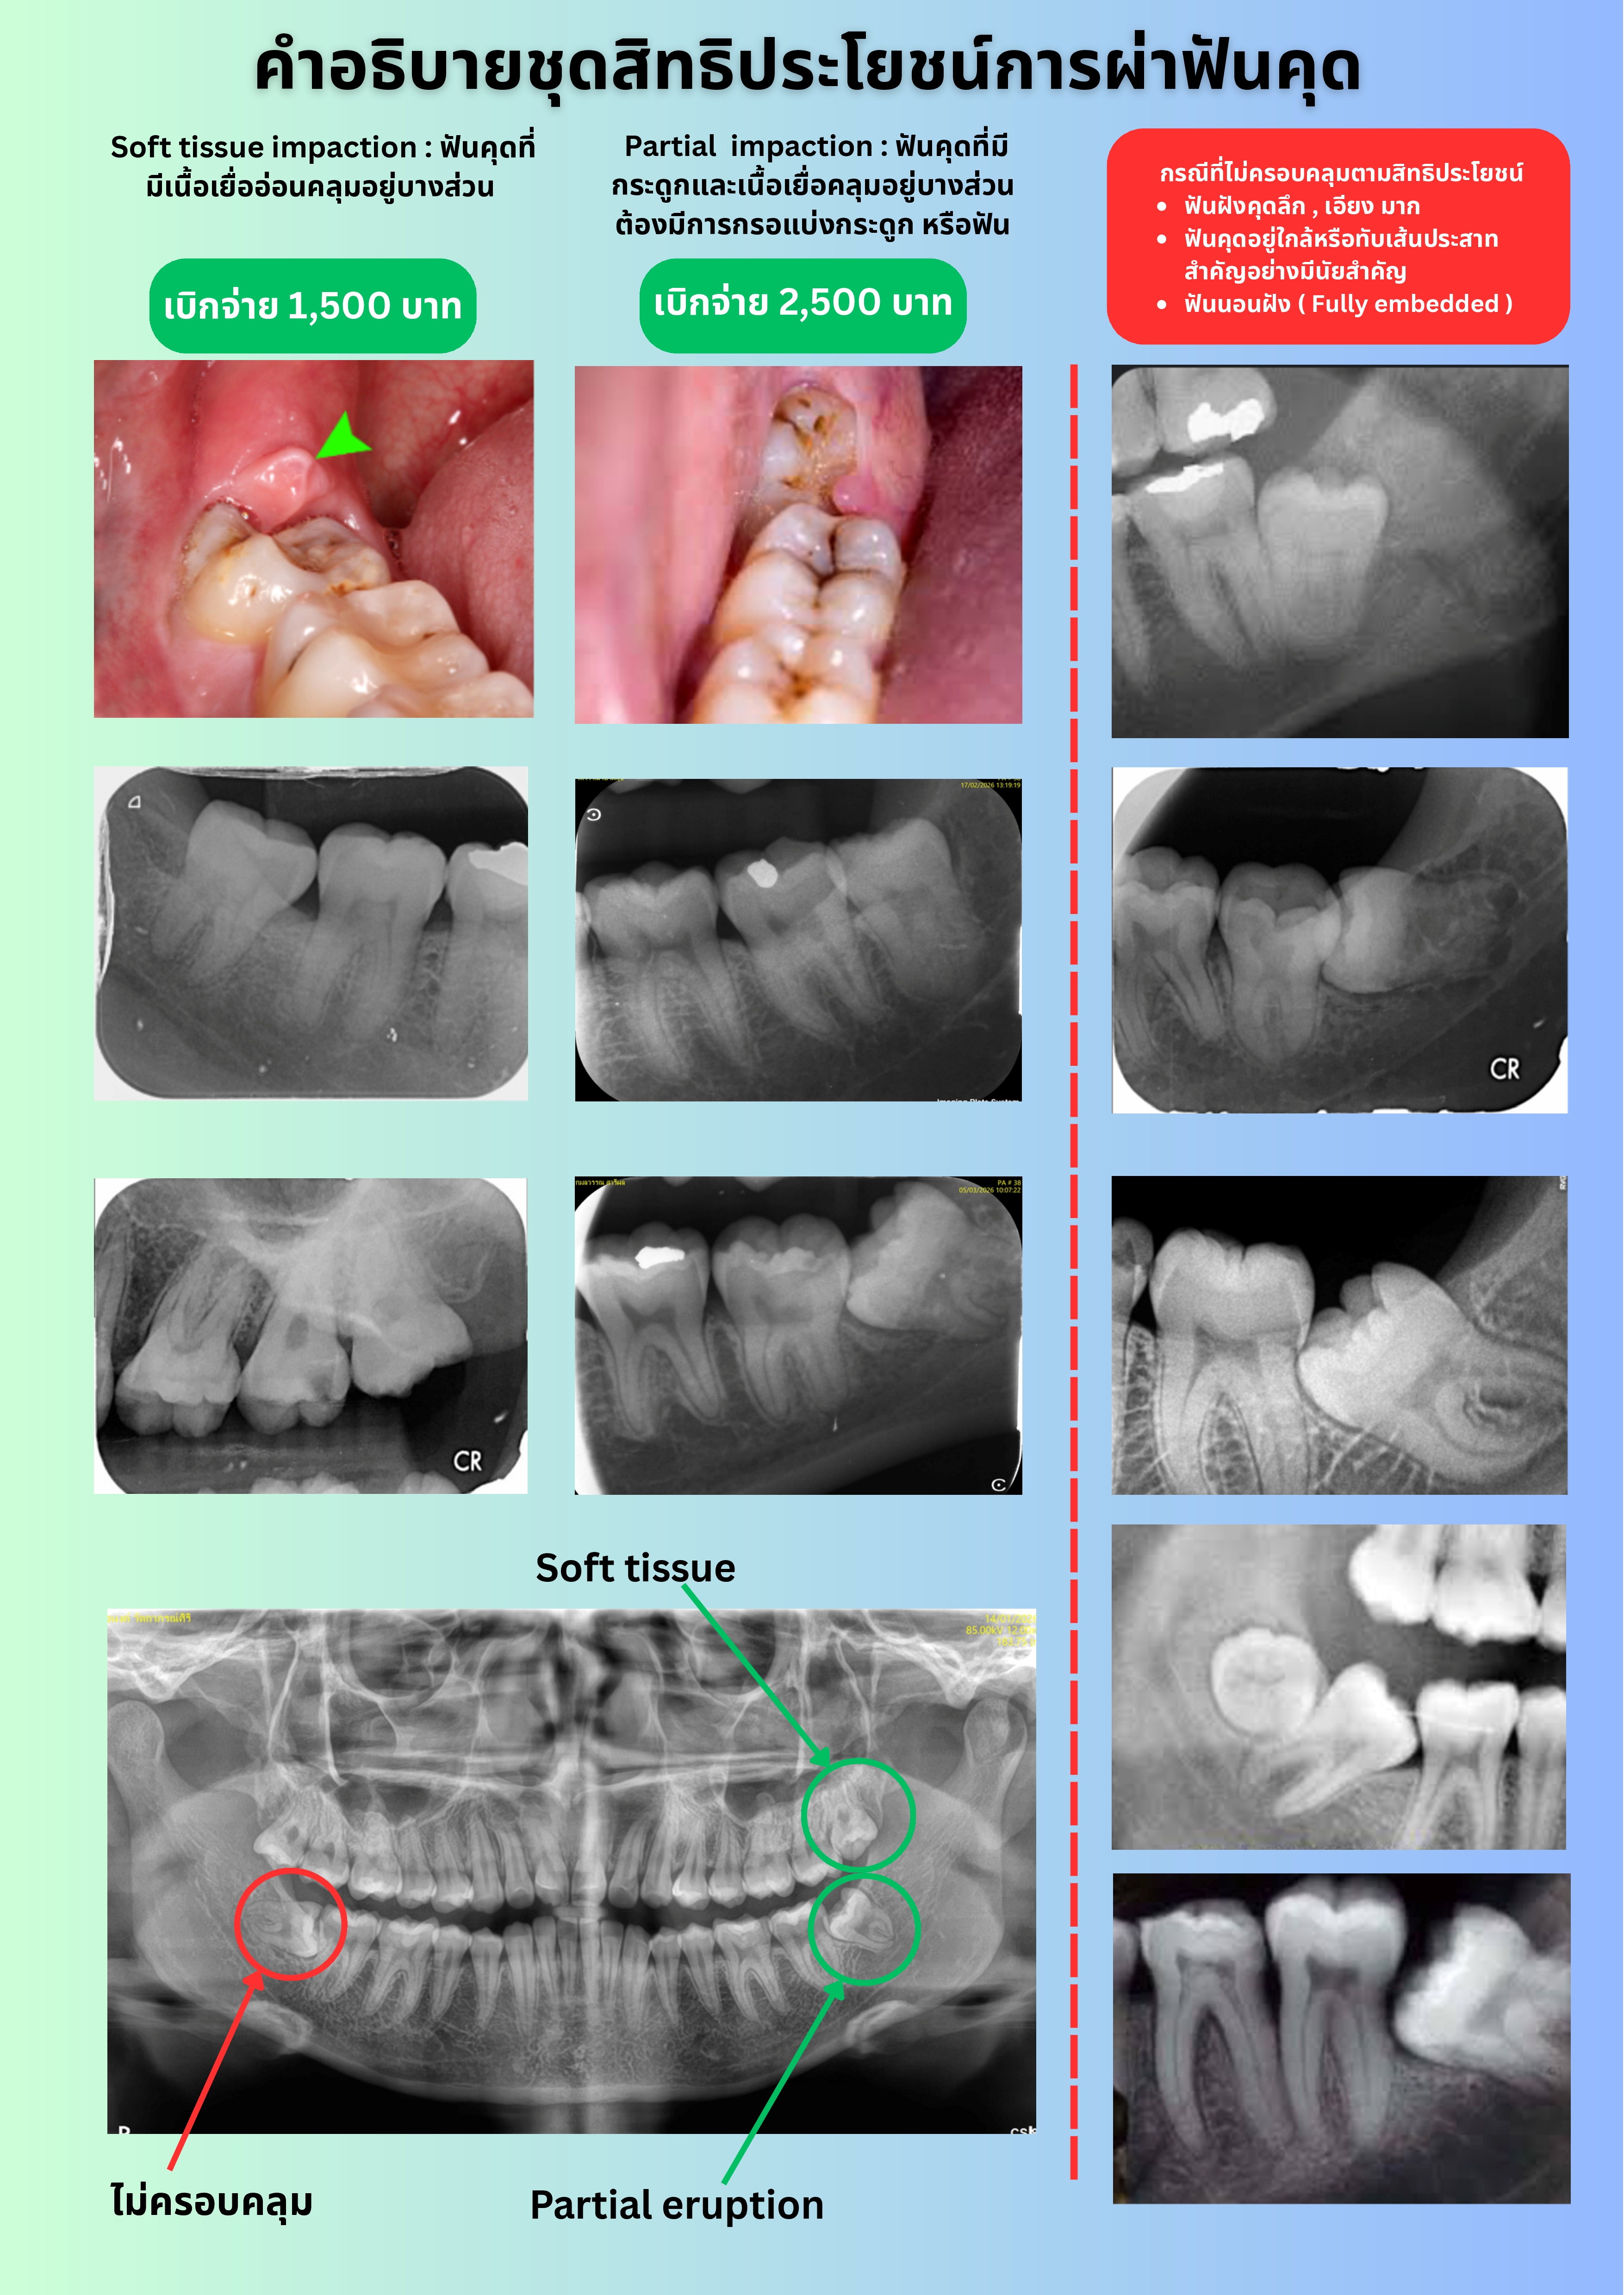

รศ.ทพ.ดร.ไชยรัตน์ เฉลิมรัตนโรจน์ นายกทันตแพทยสภา ขอชี้แจงถึงกลุ่มทันตแพทย์และผู้ประกันตน ในกรณีที่สำนักงานประกันสังคมได้เพิ่มสิทธิประโยชน์การรักษาทางทันตกรรมแก่ผู้ประกันตนโดยเพิ่มสิทธิ์ในการทำฟันเทียมถอดได้ รากฟันเทียม และการผ่าฟันคุด เพื่อให้มีความเข้าใจที่ถูกต้องทั้งการให้บริการและรับบริการ กรณีสิทธิประโยชน์ผ่าฟันคุดของประกันสังคม จะครอบคลุมเฉพาะฟันคุดที่ขึ้นไม่ได้เนื่องจากมีเนื้อเยื่ออ่อนคลุมอยู่บางส่วน (Soft Tissue Impaction Tooth) และฟันคุดที่อยู่ในกระดูกบางส่วนที่ไม่ซับซ้อน (Partial Bony Impaction Tooth) เท่านั้น

ส่วนฟันคุดที่อยู่ในกระดูกบางส่วนแบบซับซ้อน ฟันคุดที่มีกระดูกคลุมอยู่ทั้งซี่ (Completed Bony Impaction Tooth) และฟันฝัง (Embeded tooth) จะไม่อยู่ในสิทธิประโยชน์ที่ประกันสังคมกำหนดไว้